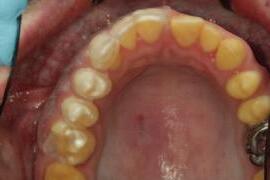

n Following clinical and radiographic assessment of the width of the keratinised mucosa, the positioning of the gingival margin in relation to the cemento-enamel junction (CEJ) and the distance of the CEJ from the bone crest, the surgical guide is tested for stability and the proposed gingival margins are approved ( Figure 3 ). To achieve an optimised outcome, the operator should envisage that at least 2mm of keratinised tissue, including at least 1mm of attached gingivae, remain intact post surgery.4 A favourable crown–root ratio and integrity of furcation anatomy must remain intact post surgery.

n During the surgery, the upper, inner edge of the window within the guide provides the surgeon with the exact site of the proposed definitive gingival margin location and in doing so, indicates the precise location of the initial internal bevel incision (Figures 4A-4C ).5